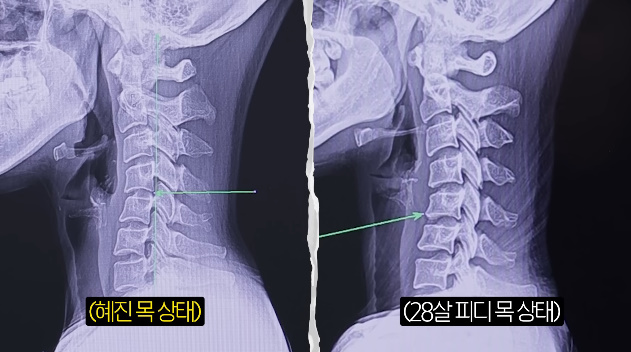

그 뒤 엑스레이 촬영을 했고, 결과물을 본 의사는 "통증이 계속 재발할수밖에 없는게 목이 역커브다"라고 심각한 상태를 지적했다. 한혜진은 "얼굴쪽으로 C자 커브가 있어야하는데 일자다 못해 뒤로 약간 가고있는것 같다"라고 놀랐고, 의사도 "역 C자다"라고 짚었다.

그는 "다행인건 신경공 자체는 좁아지지 않아서 아직 손 저림이 심하거나 그럴것같진 않다. 목디스크로 진행되면 손 저림도 심해지는거다. 신경이 눌리면 저리고 그런다. 어느정도 눌리냐에 따라 신경차단술주사 치료를 하거나 수술하는 경우도 있다. 지금 거북목이 너무 심하고 목이 좀 길기때문에 거북목이 잘 오는 스타일이다. 목이 길면 좀 더 약할 확률이 크다"고 말했다.

이에 한혜진은 "여기 환자분이 100분이 내원하면 저는 몇등정도냐"고 궁금해 했고, 의사는 "상위 10등안에 든다고 봐야한다. 안 좋은걸로"라고 말해 한혜진을 충격케 했다. 그러자 그는 "저희 피디님도 사진을 찍었다"고 말했다. 앞서 한혜진과의 비교를 위해 어린 피디도 함께 엑스레이 촬영을 진행했던 것.

하지만 의사는 "더 안좋다"고 반전 결과를 전했다. 한혜진은 다급히 PD를 불렀고, "피디님 큰일났다. 빨리 앉아라"고 말했다. 의사는 "환자분은 목이 안 아프냐"고 물었고, PD는 "아프다고 느껴본적 없다"고 털어놨다. 의사는 "핸드폰 많이 보지말라"고 지적했다. 이어 "요즘 오래 핸드폰보고 하니까 고등학생도 목디스크가 오는 경우가 있다. 물리치료나 운동치료, 집에서 할 수 있는 운동좀 배워가서 해보고 경과를 보자"고 전했다.